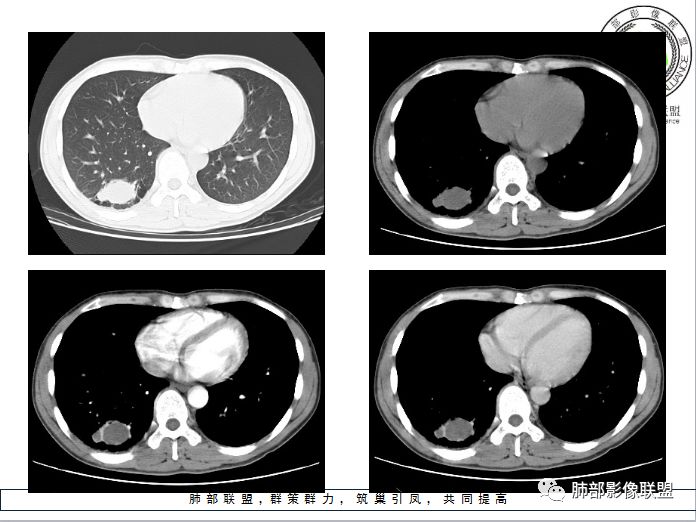

第二,看强化幅度,内无强化,但是我担心图像并不够薄,目测观察有所偏差,但是现可见薄壁样强化;从这个角度考虑,良性肿瘤就不符合了,如PSP就不太支持了,这个病变远端有分叶、有小尾巴,周围有索条状影,除非PSP合并感染,二元论,否则单纯PSP周围不会有这种表现。

第三,病变旁边胸膜区域有增厚,似乎有些血管增粗,虽然这不是隔离征好发区域;它应该偏内侧一点,但是我们应该最好有重建血管先排除隔离征;从所给图片看,病灶具体走形外面没有看见血管进入,因为是囊性病变嘛。

第四,病变为薄壁环状强化,就两种可能,

1 是病变内为囊性成分,即囊肿,周围病变考虑合并感染;      2 是病变内是干酪坏死,周围是薄壁强化,然后是一点纤维组织,再周围是一些结核的病灶;

但是有些疑惑:

首先周围病变肯定是感染性病变;索条状的,但是囊肿伴这样感染,真的很少见;

其次病变周围有索条、肺气肿,这些慢性病的改变;还有就是形态,似乎是稍长点的形态;这几点就更符合结核的表现,但是周围病灶没有树芽征,都是索条;结核这样子的干酪样坏死,也少见,壁薄呈这样,就一层纤维;附近的血管又这么粗;

但是我们先把方向锁定在炎性病变;囊肿伴感染还是结核,这两个在图片上各自特点都有,从目前条件无法完全典型的分辨出来;但是还是倾向于囊肿合并感染。